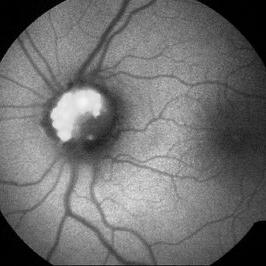

ONH Drusen

Young male with 6/6 BCVA OU AF photo showed exuberant drusen of the optic disc.

Photographer: ADITYA JYOT EYE HOSPITAL,MUMBAI,INDIA

Condition/keywords: drusen of optic disc